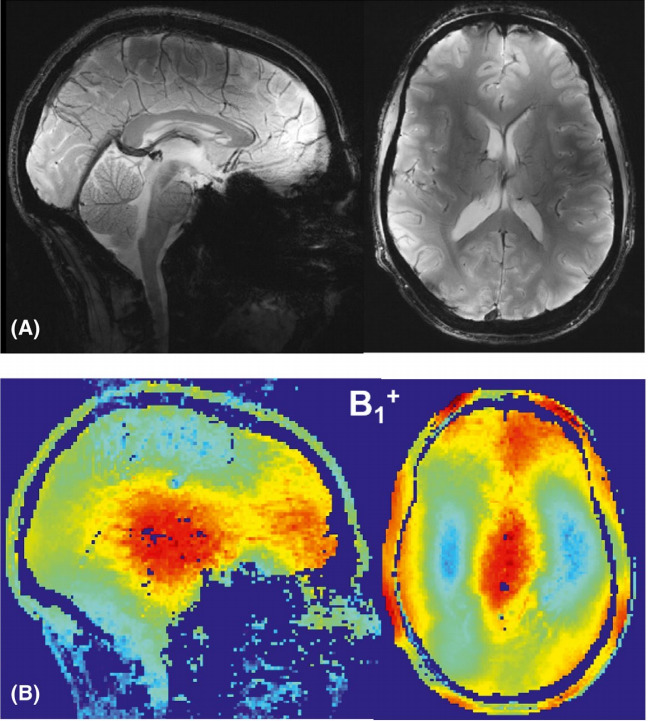

Изображение головного мозга волонтера и распределение радиочастотного магнитного поля, полученные с помощью разработанной фазированной решетки. Credit: Avdievich et al. / Magnetic Resonance in Medicine, 2021

Ученые из ИТМО изменили геометрию диполей, расположив пассивные перпендикулярно по отношению к активным. Также для обеспечения сильной электрической связи между диполями физики переместили пассивный элемент в конец решетки. Прежде чем приступить к созданию новой антенной решетки, исследователи выполнили моделирование, которое позволило оптимизировать структуру. Ее эффективность была протестирована математически и с помощью компьютерной симуляции. Кроме того, физики провели эксперимент, сделав МРТ головного мозга взрослого мужчины. Проверка показала, что подобное расположение диполей решает проблему, связанную с однородностью поля, и связи между активными диполями не появляется.